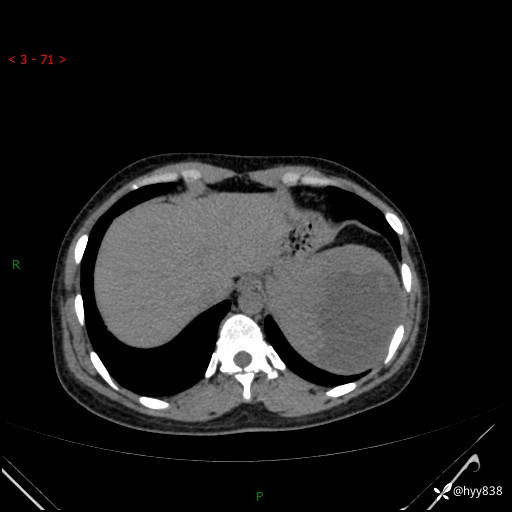

患者性别:男

患者年龄:44岁

主诉:外院超声发现脾脏占位,来我院进一步诊治。

辅助检查:CT

临床诊断:脾脏占位

脾脏CT平扫+增强(动脉期+静脉期)